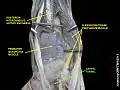

Лучезапястный сустав. Глубокий разрез.Вид спереди, ладонная поверхность.

Лучезапястный сустав. Глубокий разрез.Вид спереди, ладонная повержхность.